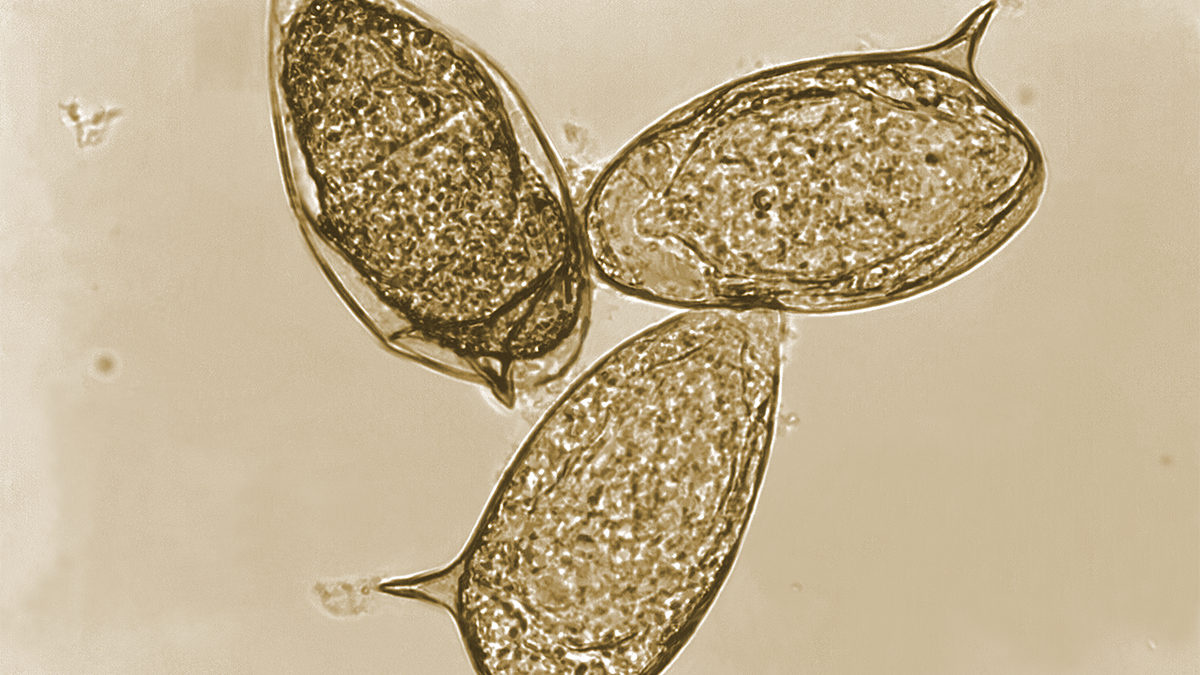

in human, dog, pig, feline, carnivore stool

lung fibrosis, seizures, secondary pneumonia

history of eating raw/pickled crustaceans

East Asia, Africa, East Russia, Indian Subcontinent, Pacific Asia, Americas

Paragonimus westermani

egg

Paragonomiasis

eating raw/pickled crustaceans